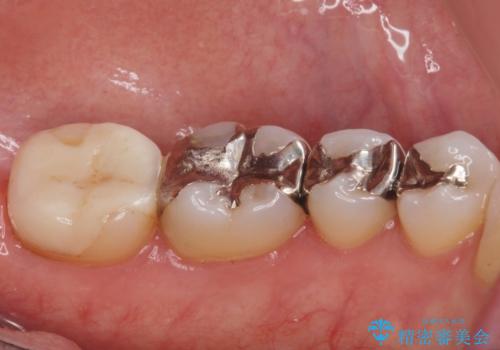

- 銀の詰め物が目立ので白くしたいとの事で来院。

とりあえず奥の二つから白くしたいとの事だったので

銀の詰め物を外し、e-maxインレーにしました。